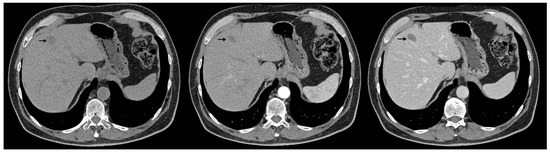

Synchronous Pulmonary and Cecal High-Grade Neuroendocrine Carcinomas Presenting as Hepatic Metastases: A Diagnostic Challenges and Literature Review

Background and Clinical Significance: Neuroendocrine neoplasms (NENs) are a group of malignancies that may remain clinically silent for many years. The presence of hepatic metastases can be the first clue leading to diagnosis. Case Presentation: We report the case of a 67-year-old man [...] Read more.

Background and Clinical Significance: Neuroendocrine neoplasms (NENs) are a group of malignancies that may remain clinically silent for many years. The presence of hepatic metastases can be the first clue leading to diagnosis. Case Presentation: We report the case of a 67-year-old man with intermittent tiredness and suspicious hepatic nodules detected on routine abdominal ultrasound. Contrast-enhanced ultrasonography showed arterial hyperenhancement with early washout, suggestive of metastases. Synchronous high-grade neuroendocrine carcinomas (NECs) of the lung and cecum were identified. Although the liver lesions were initially presumed to arise from the cecal tumor, liver biopsy immunohistochemistry was TTF-1 positive/CDX2 negative, whereas the cecal lesion was TTF-1 negative/CDX2 positive. This mutually exclusive immunophenotype confirmed two separate primary carcinomas. Given the high-grade histology, the patient received platinum-based chemotherapy and achieved a partial response. Conclusions: This case illustrates the diagnostic complexity of synchronous lesions and highlights the “mirage of the first lesion” phenomenon, in which the initially detected tumor may not represent the true primary site. A comprehensive, multidisciplinary strategy is crucial for establishing the correct diagnosis and guiding optimal management. Full article

Show Figures